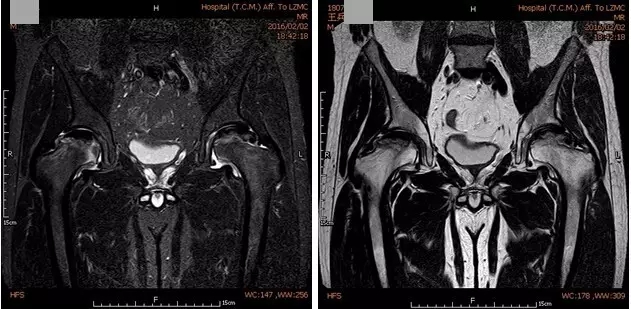

第一次术前MRI